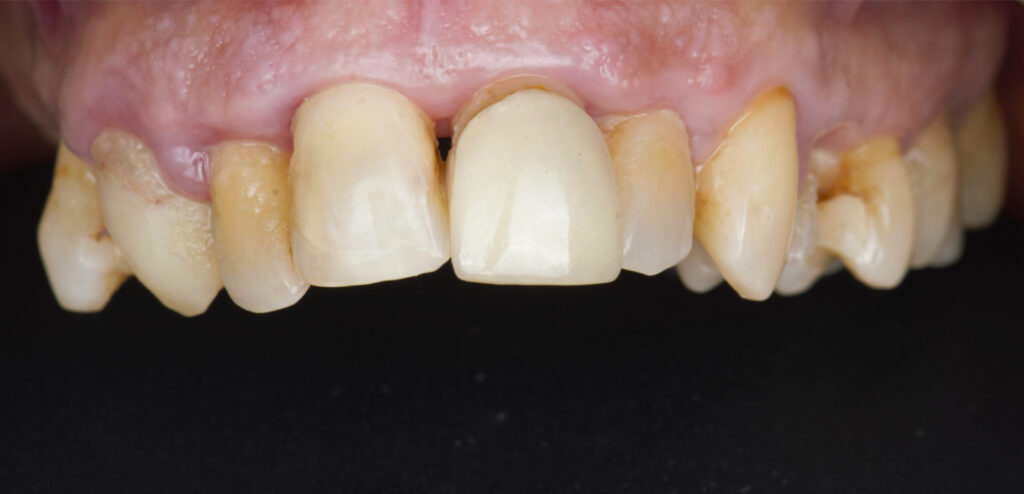

Caso clínico, Dr. José Amador Cabezas

Carga inmediata maxilar con cirugía guiada, registro fotogramétrico y provisionalización inmediata.

En este caso, el Dr. José Amador Cabezas aborda la rehabilitación completa de un maxilar superior comprometido por enfermedad periodontal avanzada, lesiones periapicales y múltiples restauraciones fallidas.

Tras la planificación protésicamente guiada y la colocación de implantes mediante cirugía guiada, se realizó el registro fotogramétrico con T-Marker sobre los Multi-Unit para capturar con precisión la posición real de los implantes y asegurar la pasividad de la estructura provisional.

Gracias a este flujo, el paciente pudo salir de la consulta con una prótesis fija inmediata el mismo día de la cirugía, iniciando así un proceso restaurador más preciso, más predecible y completamente integrado en el entorno digital.

La combinación de cirugía guiada, fotogrametría y carga inmediata permite un control preciso de la posición implantaria y una correcta pasividad protésica desde el primer día.